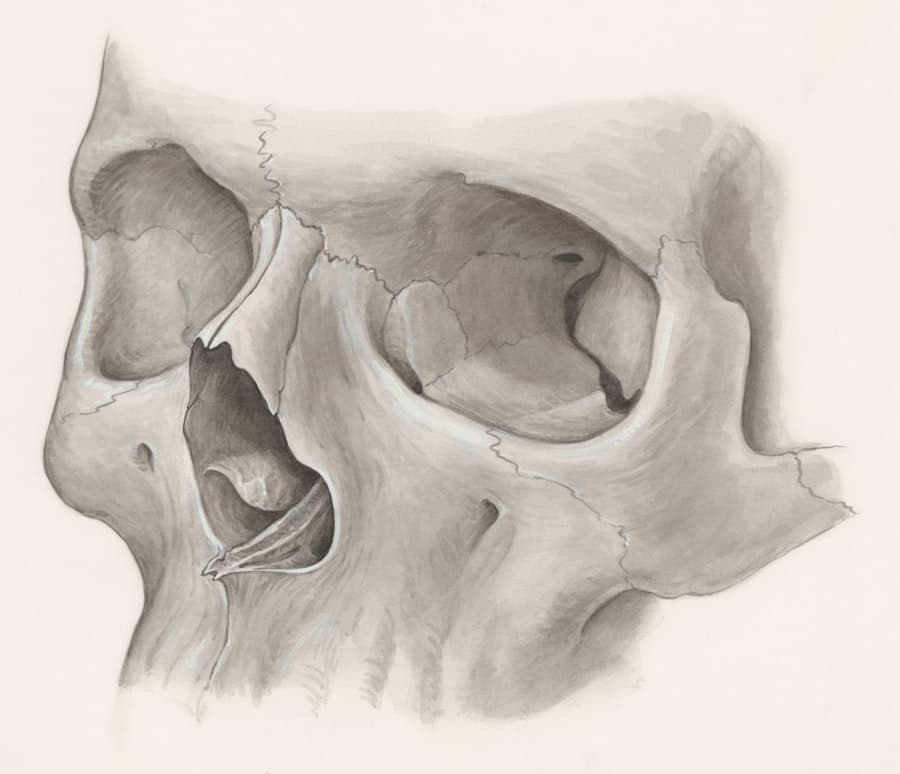

Preserving Nasal Anatomy

The closed approach often allows for a more direct preservation of the nasal tip’s delicate structures and blood supply. By working through internal corridors, Dr. Petrova can often manipulate cartilage and bone with less disruption to the nasal tip’s intrinsic support mechanisms. This can be crucial for maintaining the long-term stability and aesthetic integrity of your nose.

Maintaining the Natural Support of Your Nose

The natural scaffolding of your nose is complex. Dr. Petrova’s expertise in closed rhinoplasty focuses on understanding and working with these intricate anatomical relationships. By minimizing disruption to existing support structures, the goal is to achieve a result that is not only aesthetically pleasing but also functionally sound and enduring.

Detailed Nasal Analysis

During the consultation, Dr. Petrova will perform a thorough analysis of your nose. This includes evaluating the cartilage, bone, skin thickness, and overall nasal proportions. She will also consider your facial symmetry and how the nose contributes to your overall facial aesthetics.

Precision Through Internal Access

The internal incisions allow Dr. Petrova to access the underlying nasal framework. She can then reshape the cartilage and bone to address your specific concerns, whether it’s to refine the nasal tip, reduce a dorsal hump, or improve nasal breathing.